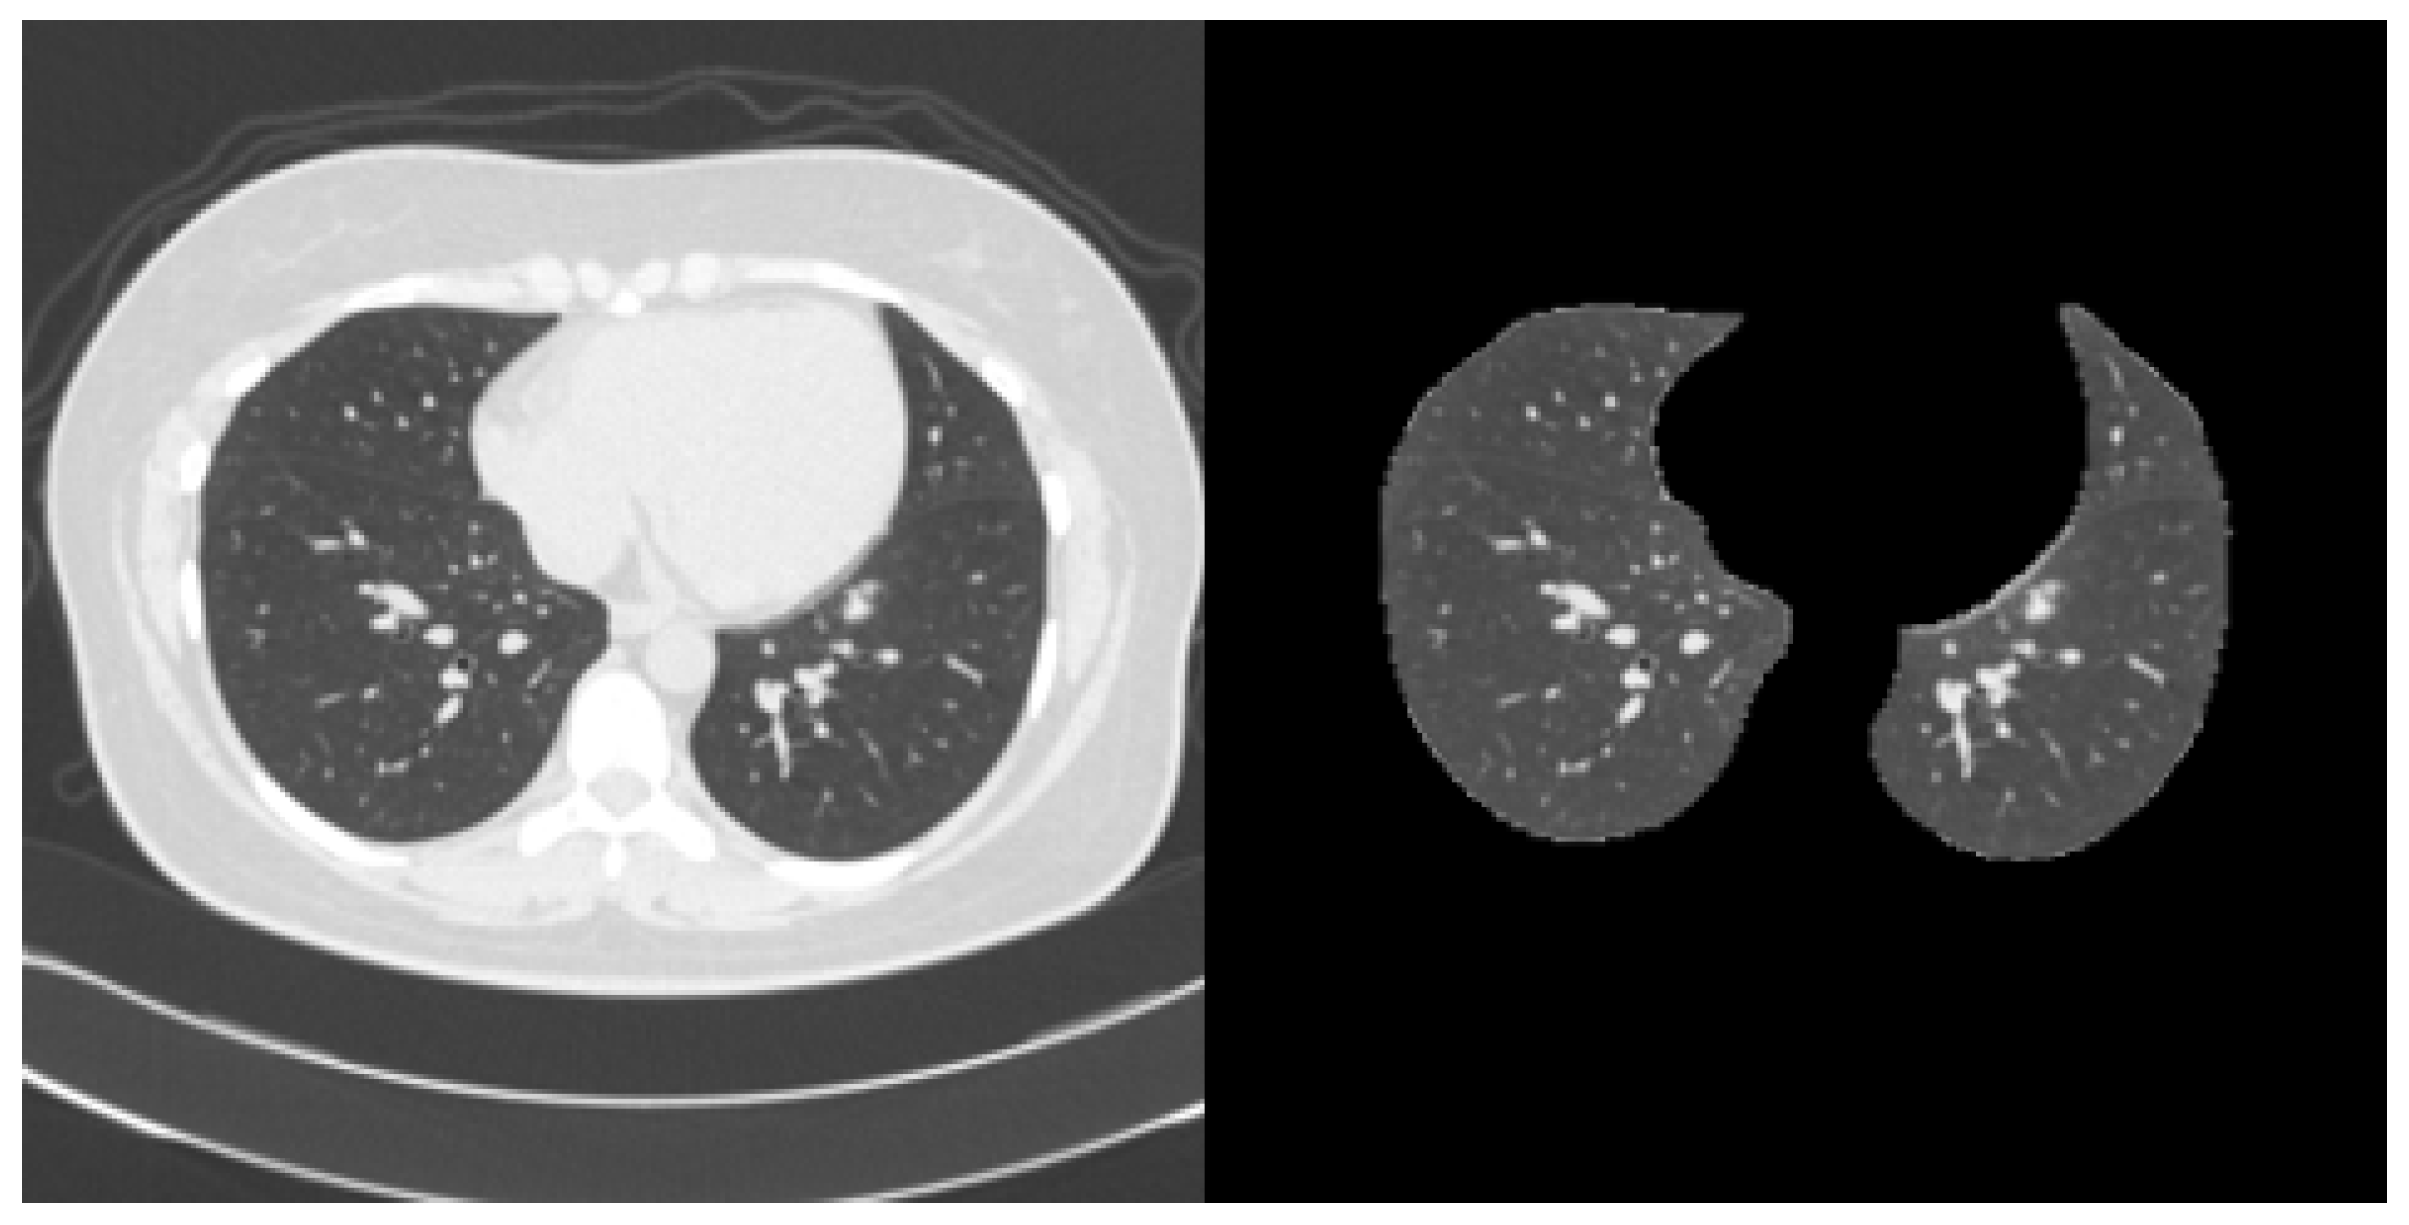

2.1. Dataset

- Hofmanninger, J.; Prayer, F.; Pan, J.; Röhrich, S.; Prosch, H.; Langs, G. Automatic lung segmentation in routine imaging is primarily a data diversity problem, not a methodology problem. Eur. Radiol. Exp. 2020, 4, 50. [Google Scholar] [CrossRef] [PubMed]